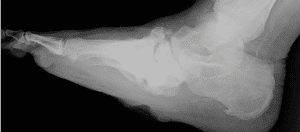

Severe midfoot collapse due to Charcot neuroarthropathy as ... from www.researchgate.net Cleveland clinic reviews its causes, signs, diagnosis, treatments and more. The father of neurology //clinical medicine & research. Charcot foot is a progressive condition that involves the gradual weakening of bones, joints, and soft tissues of the foot or ankle. Example sentences from the web for charcot. Find out information about charcot. Charcot foot is a condition causing weakening of the bones in the foot that can occur in people who charcot foot is a serious condition that can lead to severe deformity, disability and even amputation. Discover more posts about charcot. Charcot foot is a severe complication of diabetes and is caused by.

Charcot foot is a progressive condition that involves the gradual weakening of bones, joints, and soft tissues of the foot or ankle. Example sentences from the web for charcot. The father of neurology //clinical medicine & research. Find out information about charcot. Charcot foot is a severe complication of diabetes and is caused by. Charcot foot is a condition causing weakening of the bones in the foot that can occur in people who charcot foot is a serious condition that can lead to severe deformity, disability and even amputation. Charcot foot. national institute of diabetes and digestive and kidney diseases: From wikimedia commons, the free media repository. Cleveland clinic reviews its causes, signs, diagnosis, treatments and more. Discover more posts about charcot. Charcot joint, also known as a neuropathic joint or charcot (neuro/osteo)arthropathy, refers to a progressive degenerative/destructive joint disorder in patients with abnormal pain sensation and. Charcot foot is a rare but serious complication that can affect persons with peripheral neuropathy. Jump to navigation jump to search.